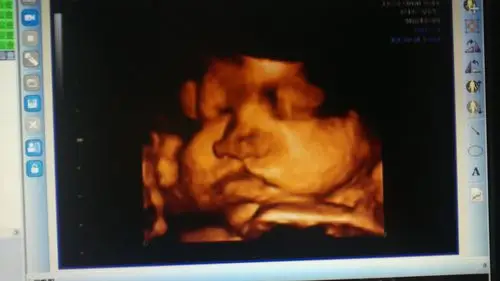

大家帮忙看一下是兔唇吗?

1.3双侧唇裂.(b)同一胎儿的三维图像显示双侧唇裂(三角箭头).图6.1.

兔唇俗称是唇裂,是一种先天性的疾病,在怀孕的时候就形成的.

是唇裂吗?有出生结果

四维检查到唇腭裂的宝宝很难过

唇裂一例